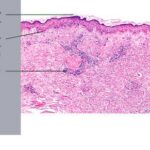

Patients with SJS often present with fever and malaise and develop a cutaneous eruption consisting of “flat atypical targets,” or erythematous or purpuric macules, many with central epidermal necrosis or blister formation. The lesions usually start on the trunk and spread centrifugally. Again, epidermal detachment is <10% of the body surface area . |

TEN, also referred to as Lyell’s syndrome, is characterized by widespread, full-thickness epidermal necrosis involving >30% of the body surface area . These patients also have systemic symptoms and may initially present with diffuse erythema and skin tenderness, followed by the development of large, flaccid bullae and detachment of the epidermis in sheets . SJSfTEN overlap is used to refer to patients with epidermal detachment between 10% and 30% of the body surface area . TEN has a high mortality rate because offluid loss and sepsis. |

intensity of epidermal necrosis varies from vacuolated individual keratinocytes surrounded by lymphocytes (satellite cell necrosis) at the basal unit to confluent necrosis in association with intraepidermal and subepidermal vesicles. The dermal infiltrate comprises lymphocytes and histiocytes. Eosinophils may also be present. Although one study has noted a significant number of eosinophils in drug-induced EM, this has not been noted by others. In the authors’ estimation, a generous number of eosinophils exclude EM. One study has found that an acrosyringium concentration of apoptotic keratinocytes in EM is a clue to a drug etiology . In early lesions of SJSITEN, apoptotic keratinocytes are observed scattered in the basal layer of the epidermis. In established lesions, there are numerous necrotic keratinocytes, even full-thickness epidermal necrosis, and a subepidermal bulla. The dermal inflammatory infiltrate is sparser in TEN than in EM (Fig. 9-278). Extravasated erythrocytes are commonly found within the blister cavity. Melanophages within the papillary dermis occur in late lesions. Eccrine epithelium shows a variety of changes from basal cell apoptosis to necrosis of the duct. |

In general, EM shows less epidermal necrosis, more dermal inflammation, and exocytosis, whereas SJS and TEN reveal more epidermal necrosis, less dermal inflammation, and exocytosis. However, due to the overlapping histologic features among EM, SJS, and TEN, histologic examination-while important for recognizing the spectrum of disorders-is not reliable for classifying the disease. Correlation with clinical presentation is essential. |